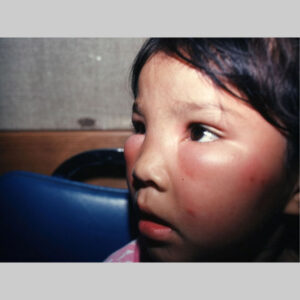

Angioedema is the swelling of deep dermis, subcutaneous or submucosal tissue due to vascular leakage.1 It was first described in 1586.2 Other terms, such as giant urticaria,3 Quincke edema,4 and angioneurotic edema,5 have also been used in the past to describe this condition. Clinically, angioedema is usually nonpitting and nonpruritic. The area of involvement is often skin-colored or slightly erythematous. Depending on the area of swelling, pain can be absent or mild, as in most peripheral or facial swelling, or can be very severe, as in gastrointestinal angioedema. Laryngeal swelling is life-threatening. It should be treated as a medical emergency.

Patients usually describe swelling of the face (eg, eyelids, lips), tongue, hands, and feet. It can be acute or chronic, and each episode of angioedema may last a few hours to a few days. A local burning sensation and pain can be observed without pronounced itchiness or local erythema. Abdominal pain can sometimes be the only presenting symptom of angioedema. Throat tightness, voice changes, and trouble breathing may indicate airway involvement.

For skin involvement, examination can easily identify areas of swelling with or without erythematous skin, often with ill-defined margins. Some cases of angioedema occur in patients with urticaria.